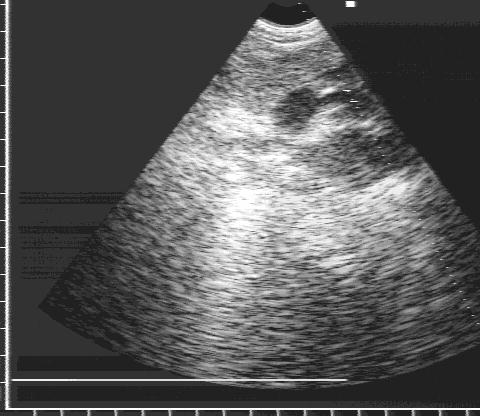

Врожденный дефект, проявляющийся аневризматической дилатацией левого предсердия без заболеваний левого желудочка или митрального клапана (рис.90).

Врожденная аневризма левого предсердия.

Рис.90.

Врожденная

аневризма левого

предсердия.

1. Большое объемное образование, связанное с левым предсердием.

2. Может быть сдавление стенки левого желудочка аневризматическим телом.

3. Изменение позиции камер сердца из-за смещения их объемным образованием.